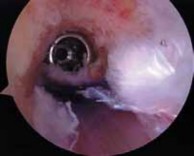

1. The guidewire is then advanced, and, if correctly placed, the tibial tunnel is made with a 10-mm drill.

2. The tunnel is inspected with the arthroscope for wall compromise from the previous tunnel (

TECH FIG 2B

). This can be performed by placing the arthroscope up the tibial tunnel.

1. If there is concern for fixation strength with the interference screw, the tibial bone plug can be reinforced by tying the suture previously placed through the bone plug over a post just distal to the tibial tunnel.

2. It is then brought back into the notch so that the back wall can be inspected (

TECH FIG 2C

).

11. At this time, the tunnel also is inspected to ensure that the previous femoral tunnel does not compromise the new tunnel.

TECH FIG 2 • A. Placement of the tibial tunnel guidewire just anterior to the native posterior cruciate ligament (PCL). B. Appearance of the revision tibial tunnel using the arthroscope to inspect for compromise from the index procedure. C. After reaming the femoral tunnel to a depth of 10 mm, the tunnel is inspected to ensure the posterior wall is intact.